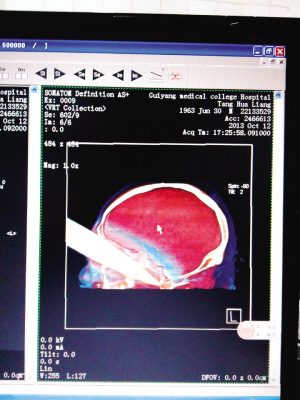

影像:脑部差点刺穿

为精确还原刀刃在脑内的情况,必须要有影像。“但这个伤做影像很难。”杨夏医生解释道,由于是金属物质,不能做核磁共振,也不能做影像检查,金属会造成投影中出现伪影,照出来的影像照片经常是黑巴巴一片,掩盖了刀刃周围的正常组织,也无法判断刀刃在脑中的真实情况。

影像科的工作人员启动了最先进的特殊处理技术,经一个多小时的后期处理,还原了脑内情况:插入伤者唐某的刀刃已有12.5公分,全刀长约30公分,刀刃有16.5公分,“也就是说,刀刃几乎全部由眼眶插入了脑部。”影像医生说,从图像中能看到,刀刃刚巧划过伤者颅底,触及左侧颈椎椎体,差点把整个脑袋刺穿。